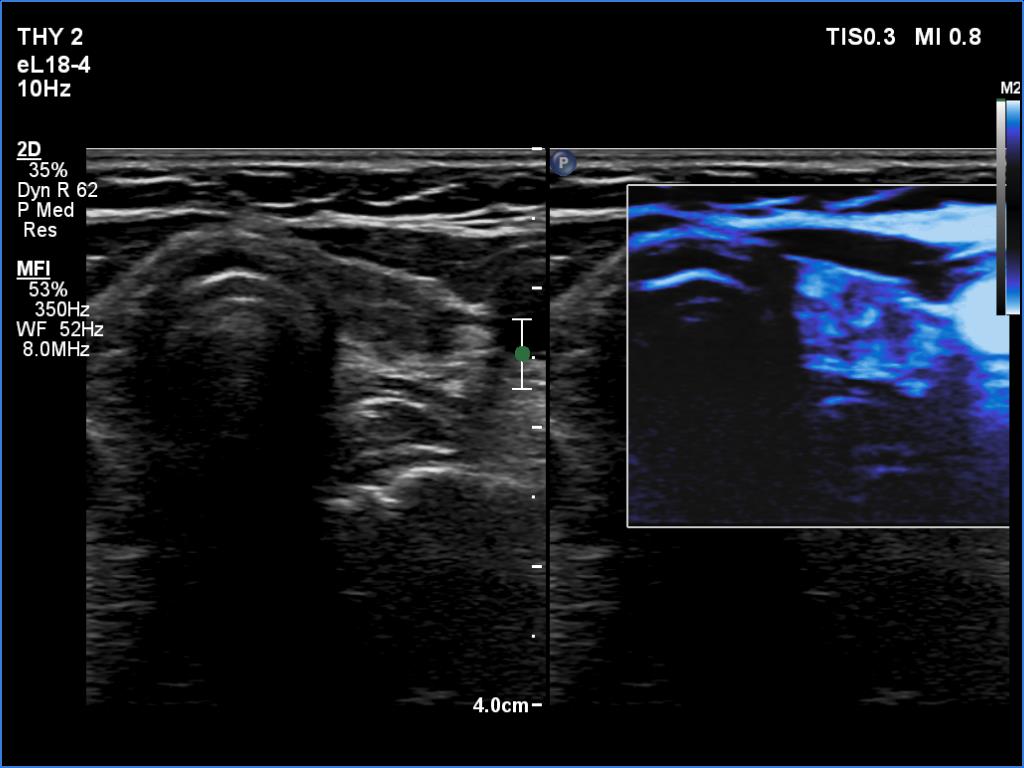

Elastography - case 650 (ultrasonographic picture 11)

Left lobe, transverse scan, microflow imaging.